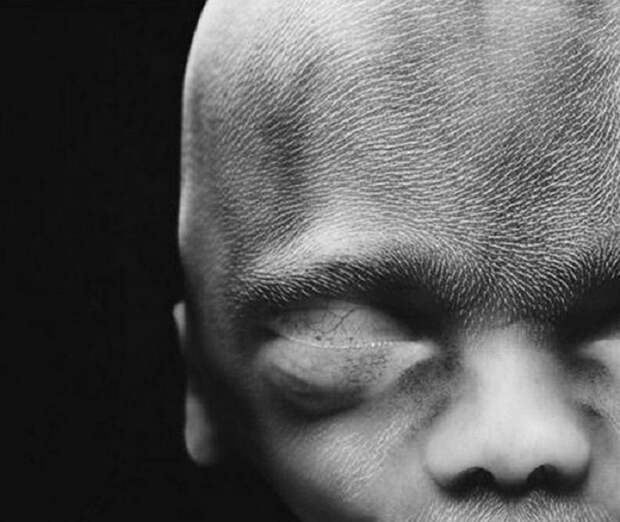

Такие крошечные суставы и будущие косточки.  Постепенно формируется разрез глаз.

Постепенно формируется разрез глаз.